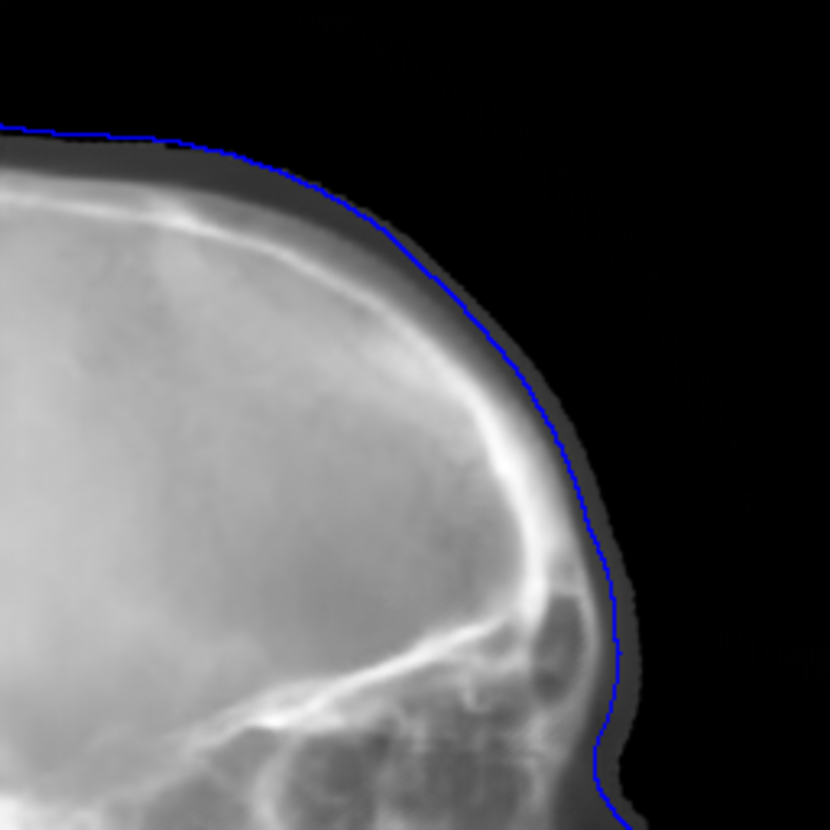

Fig. 10: Synthetic cephalogram examples from 2D CBCT projections. The top two rows are two patches respectively, while the bottom row is a complete stitched cephalogram. In the top row, the blue curve is the outline of the target patch, while the red and green curves are the outlines for the 0superscript00^{\circ} and 180superscript180180^{\circ} projections, respectively. In the middle row, the cranial sutures indicated by the arrow in (j) are not visible in (k) nor in (l); the sella turcica indicated by the arrow in (k) is distorted. In the bottom row, the vertebrae indicated by the arrow in (r) are more accurate than those in (q). The line in (m) marks the position for line profiles in Fig. 12. For the 1-projection output and the 2-projection output, the RMSE (left), PSNR (mid) and SSIM (right) values w. r. t. the target are displayed in the corresponding subcaptions.

The cephalogram synthesis results of two patches and one complete stitched cephalogram are displayed in Fig. 10. In the top row, the blue curve is the outline of the target patch, while the red and green curves are the outlines for the 0superscript00^{\circ} and 180superscript180180^{\circ} projections, respectively. Consistent with the relationship in Fig. 4, the blue curve is between the red and green curves. Since the 180superscript180180^{\circ} projection (green channel) has larger area than the 0superscript00^{\circ} projection (red and blue channels), the region near the boundary appears green in the RGB input patch in Fig. 10(c). Fig. 10(d) is the target output. Fig. 10(e) is the output using the 0superscript00^{\circ} projection only, where the outline has large deviation from the target blue curve. In contrast, in Fig. 10(f) where the dual projections are used, the outline is closer to the target blue curve. In the middle row, the sella turcica in the 1-projection output has large distortion, as indicated by the arrow in Fig. 10(k), compared with that in the target patch. On the contrary, the sella turcica in the 2-projection output (Fig. 10(l)) preserves its shape. These observations highly demonstrate the benefit of using dual projections.